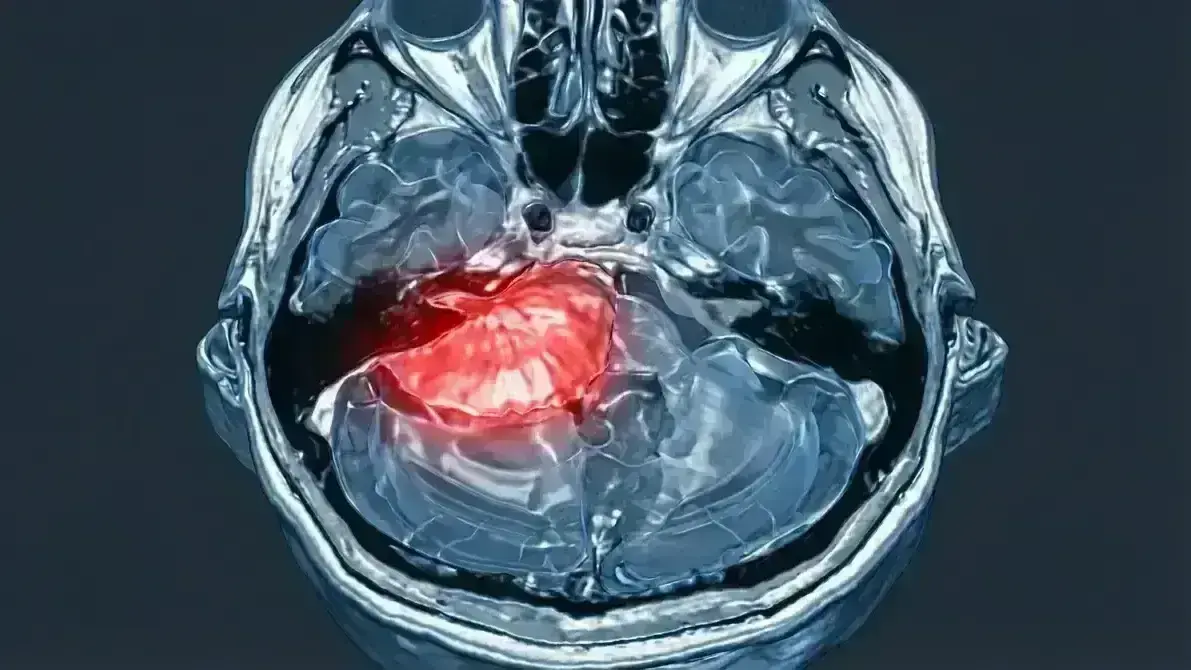

Ressecção de Meningeoma do Ângulo Pontocerebelar

Procedimento para remoção de tumor meningeoma originado das células da aracnoide na região do ângulo pontocerebelar (CP Angle) — espaço triangular entre o cerebelo, a ponte (tronco encefálico) e a orelha interna. Diferente do neurinoma, o meningeoma nasce fora dos nervos, mas comprime-os à medida que cresce.

Estes tumores geralmente são benignos (WHO grau I), circunscritos e de crescimento lento, mas podem atingir tamanhos consideráveis, moldando-se ao redor de vasos e nervos como cera derretida que solidifica, tornando a dissecção um exercício de paciência e precisão microscópica.